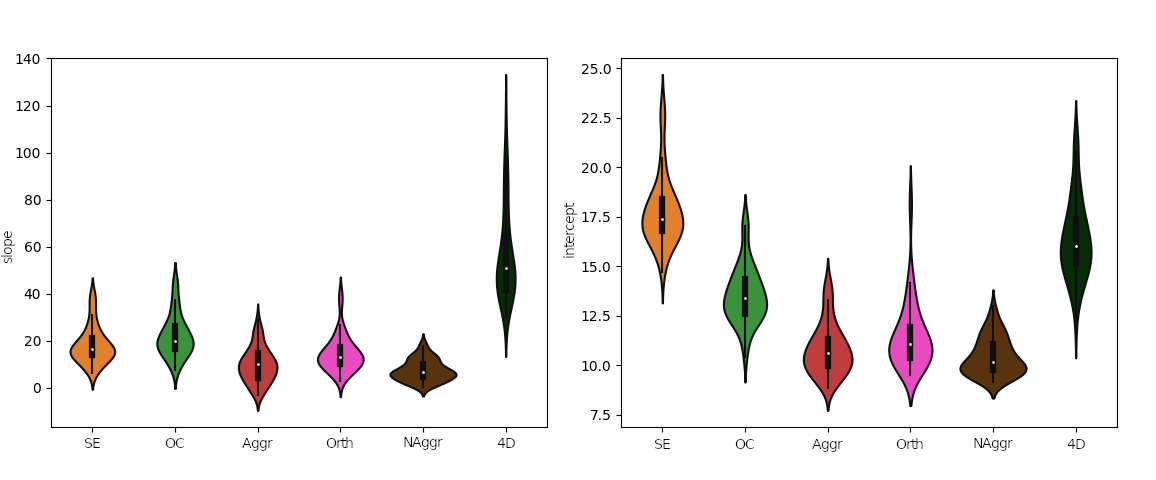

Alternative ICA based denoise (sequential)

What is the best way to denoise the data after ICA?

Regression based:

Aggressive approach: nuisance regression using only the rejected components.

Non aggressive (partial regression) approach: all the components are considered, but only the rejected components are regressed out of the data.

Orthogonalised approach: the rejected components are orthogonalised with respect to the other components.

4D-based approach (similar to M/EEG): reconstruct volumes on noise, then subtract it from the original data.

Effect of denoising approach is significant for slope (F(5,354)=177.6, p<0.001) and intercept (F(5,354)=225.7, p<0.001) of the linear regression model

DVARS vs FD

Group level, DVARS vs FD

Slope

Intercept

↓

↓

Results: motion removal

Moia et al. 2021 (NeuroImage)